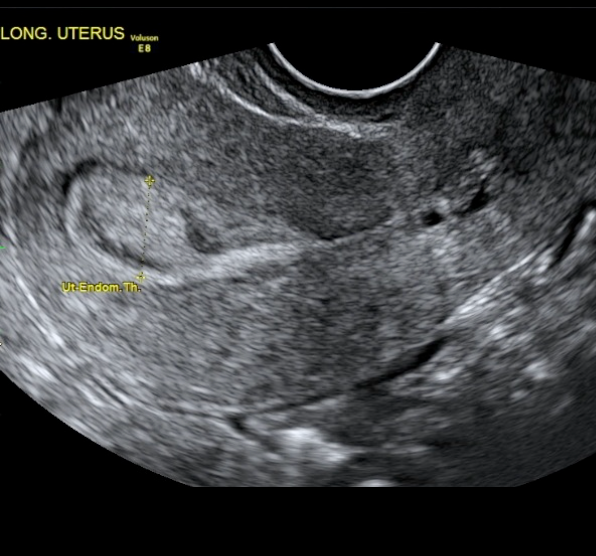

O diagnóstico inicial geralmente é suspeitado por exames de imagem, sendo os mais utilizados:

Fonte: IPGO Medicina da Reprodução (https://ipgo.com.br/as-causas-de-infertilidade-na-mulher-e-os-exames-para-o-diagnostico/)